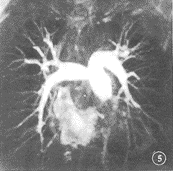

2.3 对病变的显示:2例临床怀疑肺栓塞病人其一显示了右下肺动脉的多支血管缺失(图5),另1例由于屏气不佳而致影像模糊。2例肺动静脉畸形在增强后的第Ⅰ及第Ⅱ期图像上均清晰显示,并可区分引流动脉及静脉(图6)。1例胸腺瘤和1例淋巴瘤在增强后第Ⅰ期均只见轻度强化,第Ⅱ期则见明显的周边强化。1例淋巴管囊肿未见强化。

图5 肺栓塞病人,右下肺动脉内及前基底段缺支,核素检查示右下肺内基底段,前基底段,背段多发肺栓塞